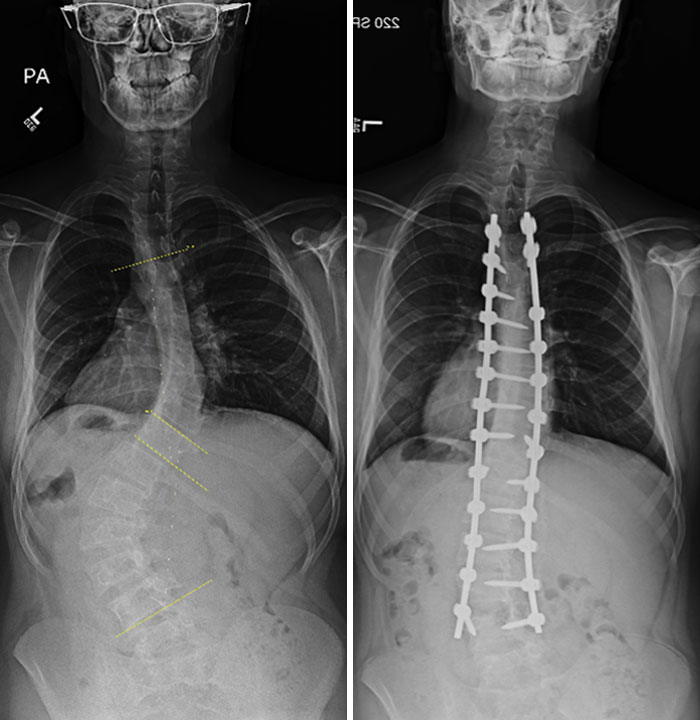

X-Rays Before And After Spinal Fusion Surgery For Scoliosis. I Had Surgery At 12 After The Curvature Continued Getting Worse Despite Interventions Being Taken

15 years since surgery and I have no back-related issues. The only issues are caused by the scar tissue from the auto-bone graft from my hip

6 Years Ago Today I Had A Surgery To Straighten Up My Spine, This Is The Before And After Result. I Gained 5 Cm With The Process